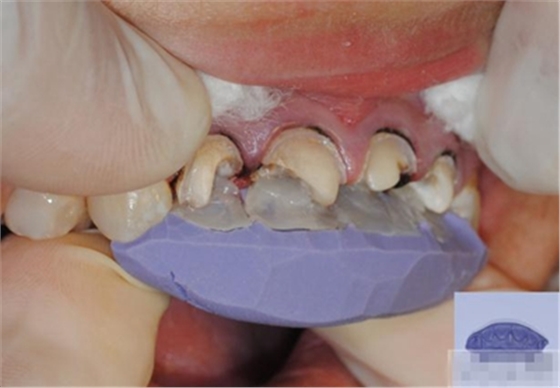

樹(shù)脂修復(fù)【診斷蠟型制作】美學(xué)蠟型可以使患者對(duì)可以達(dá)到的修復(fù)效果有直觀的了解,而且,患者也可以依據(jù)自己的美學(xué)素養(yǎng)對(duì)修復(fù)效果提出修改的意見(jiàn);

制作舌側(cè)背板

使用事先制作完成的硅橡膠模板。它是由技師在做好的美學(xué)蠟型的模型上制作的。這樣的方法為牙醫(yī)提供了許多便利:

b,應(yīng)用硅膠模板牙醫(yī)可以觀察到牙體預(yù)備量;

c,硅膠模板使牙體修復(fù)簡(jiǎn)化,可以首先堆塑牙體的舌側(cè)面,這也是Dr.Vanini分層堆塑技術(shù)的基礎(chǔ),使用硅膠制作的膠刷會(huì)使堆塑更加簡(jiǎn)單;